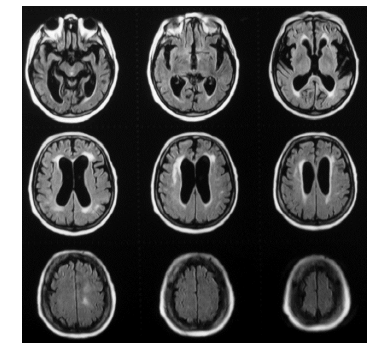

Observe a sequência de imagens abaixo e assinale a alternativa que apresenta sua correta leitura.